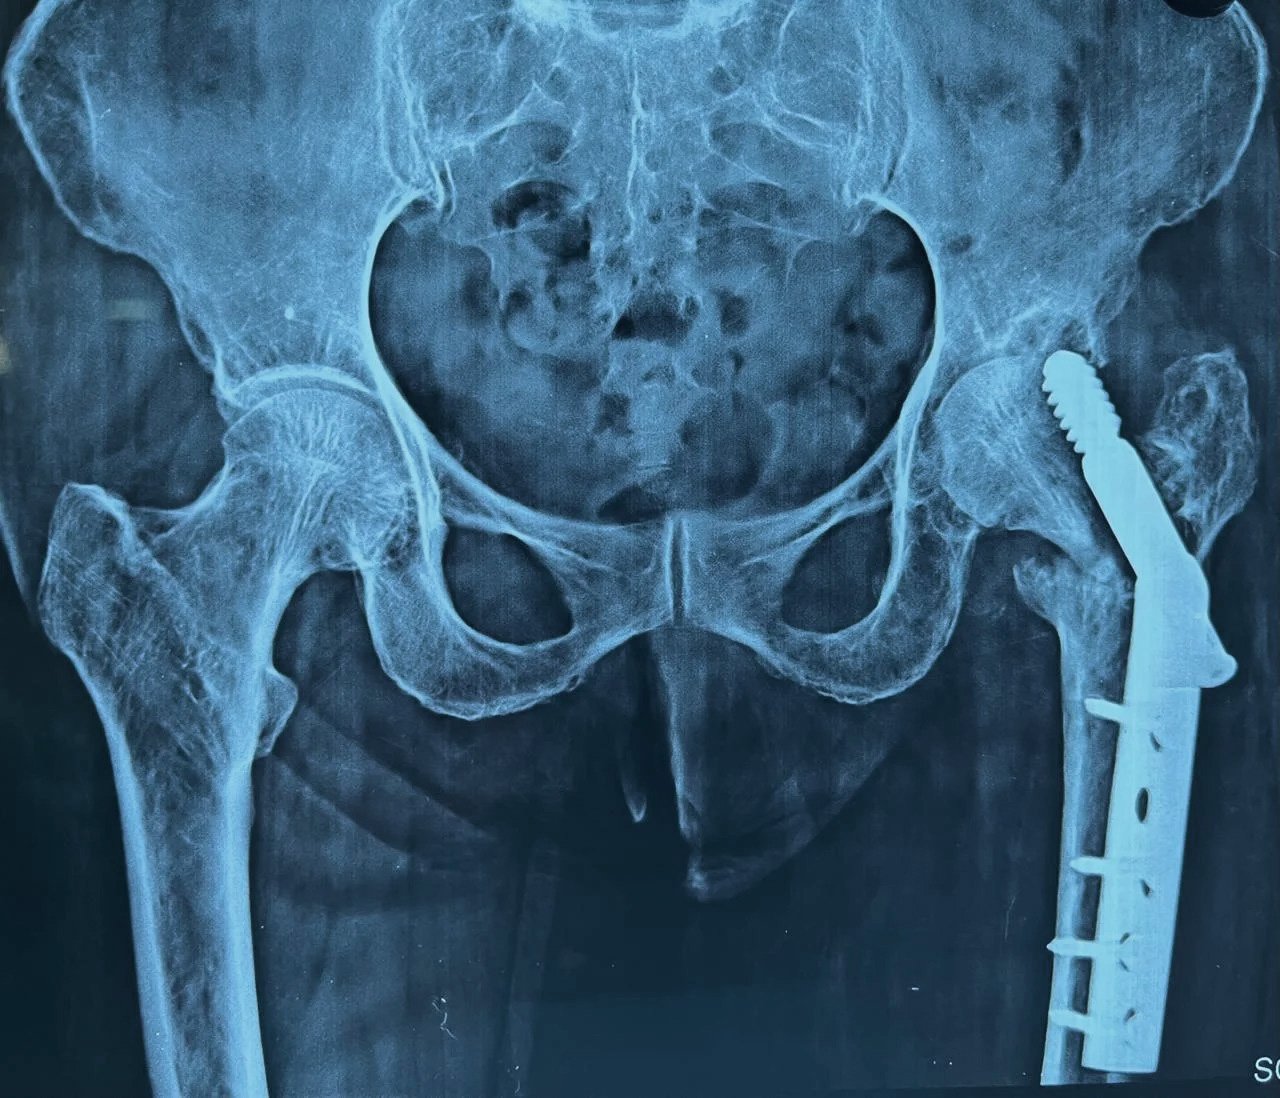

DHS Failure & Long Stem THR

Pre-Op X-Ray